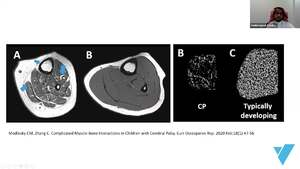

-Why are bones weak in children with cerebral palsy